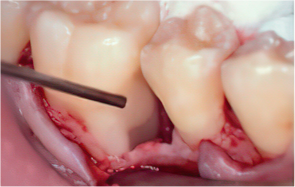

엠도게인 수술과정

-

STEP 01

잇몸을 절개

STEP 02

Scaling Root Planning을 실시

STEP 03

치석 및 치태 등 제거

STEP 04

엠도게인 도포

STEP 05

클렌징

STEP 06

판막을 봉합